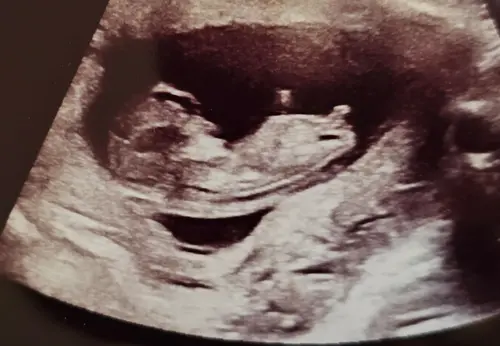

Hi, 12 weken nu. Heeft iemand een idee 😇🩷🩵